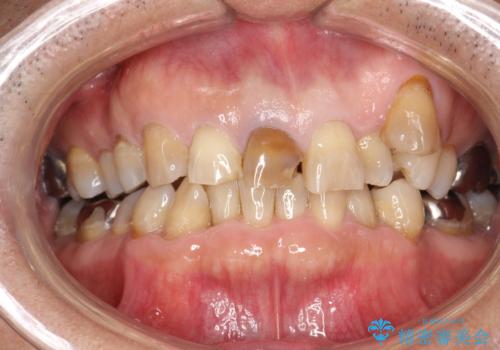

20代女性 前歯の不良な詰め物から大きな病気へ→根本から治療

前歯に大きなプラスチックの詰め物がされており、そこから感染したばい菌により根の先に大きな病気がつくられてしまっていました。

炎症が急性化し、歯ぐきの裏は膿で大きく腫れあがっていたため、切開・排膿・ガーゼドレーンにより腫れを落ちつかせた後(Dr奥村に協力してもらいました)、精密根管治療を行いました。

プラスチックを全て除去したことで、本来の歯の形態は失われるため、根管治療後の封鎖も兼ねて、被せもので修復します。